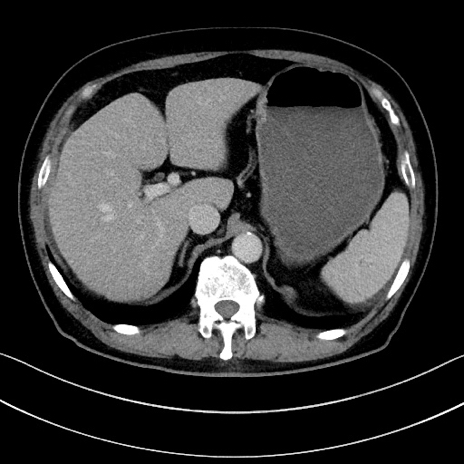

症例15(横断像)

【症例】70歳代男性

【主訴】腹痛

【現病歴】今朝から腹痛あり。全体的に痛い。特に左上の方。排ガスが今日はない。冷や汗が出る。

【既往歴】直腸癌術後

【身体所見】左側腹部〜上腹部に圧痛あり。腹膜刺激症状明らかなではない。軽度反跳痛。左下腹部に術後瘢痕あり。

【データ】WBC 7700、CRP 0.02